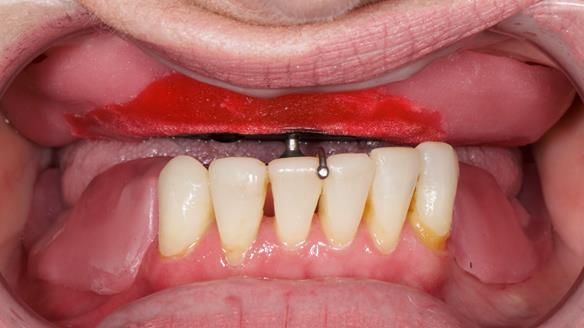

This newsletter describes the full protocol workflow of a complete upper denture and a lower partial denture for Jo.

The clinical situation and treatment process is shown in detail below. I provided the clinical work. Rowan Garstang provided the technical work. This treatment took 25 visits over a period of 12 months.